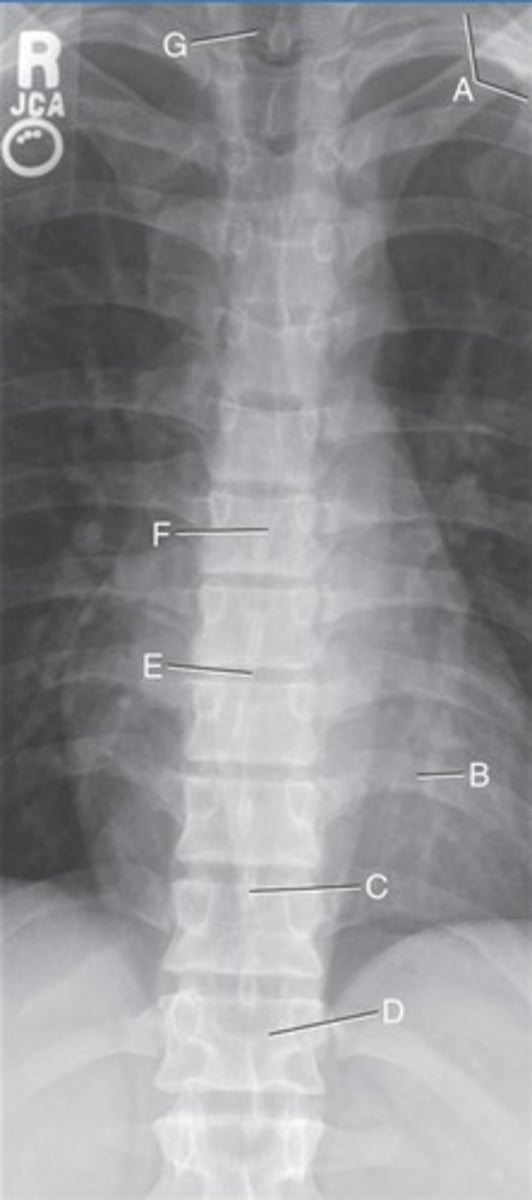

L 1st posterior rib

A.

L 10th posterior rib

B.

T11 spinous process

C.

T12 body

D.

T8-9 intervertebral disk space

E.

T7 body

F.

T1 body

G.

AP t-spine

What position?